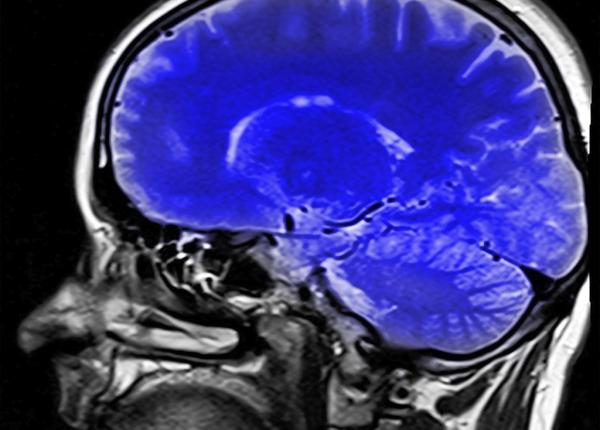

Accident vascular cerebral, cum îl prevenim și cum îl tratăm? Dr Adriana Dulămea explică

Conf Univ Dr Adriana Dulămea arată care sunt mijloacele pe care le avem la îndemână pentru a preveni și pentru a trata un accident vascular cerebral (AVC).

10 complicații ale unui accident vascular cerebral. Explicații neurolog

Accidentul vascular cerebral, tot ce îl poate provoca. Dr Adriana Dulămea detaliază